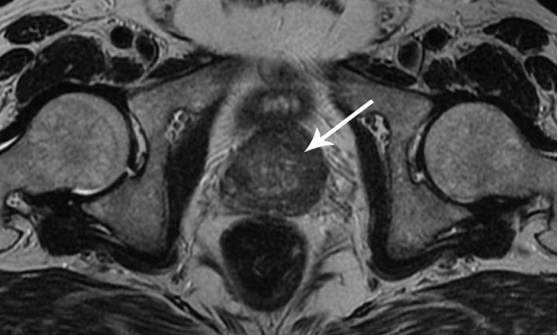

Želim vam pokazati nekoliko slika, tako da sami možete vidjeti što se događa s genitalno-mokraćnim sustavom i drugim organima muškarca koji nema seks.

Ovako izgleda upala prostate uzrokovana stagnacijom sperme (kada se testisi ne isprazne). Trajna upala prvo dovodi do adenoma prostate, a kasnije i do raka prostate (na temelju statističkih podataka, 38% muškaraca umre zbog toga). U nedostatku seksa, to se uvijek događa, razlog zbog čega se adenom prostate naziva 'bolest starijih osoba'.